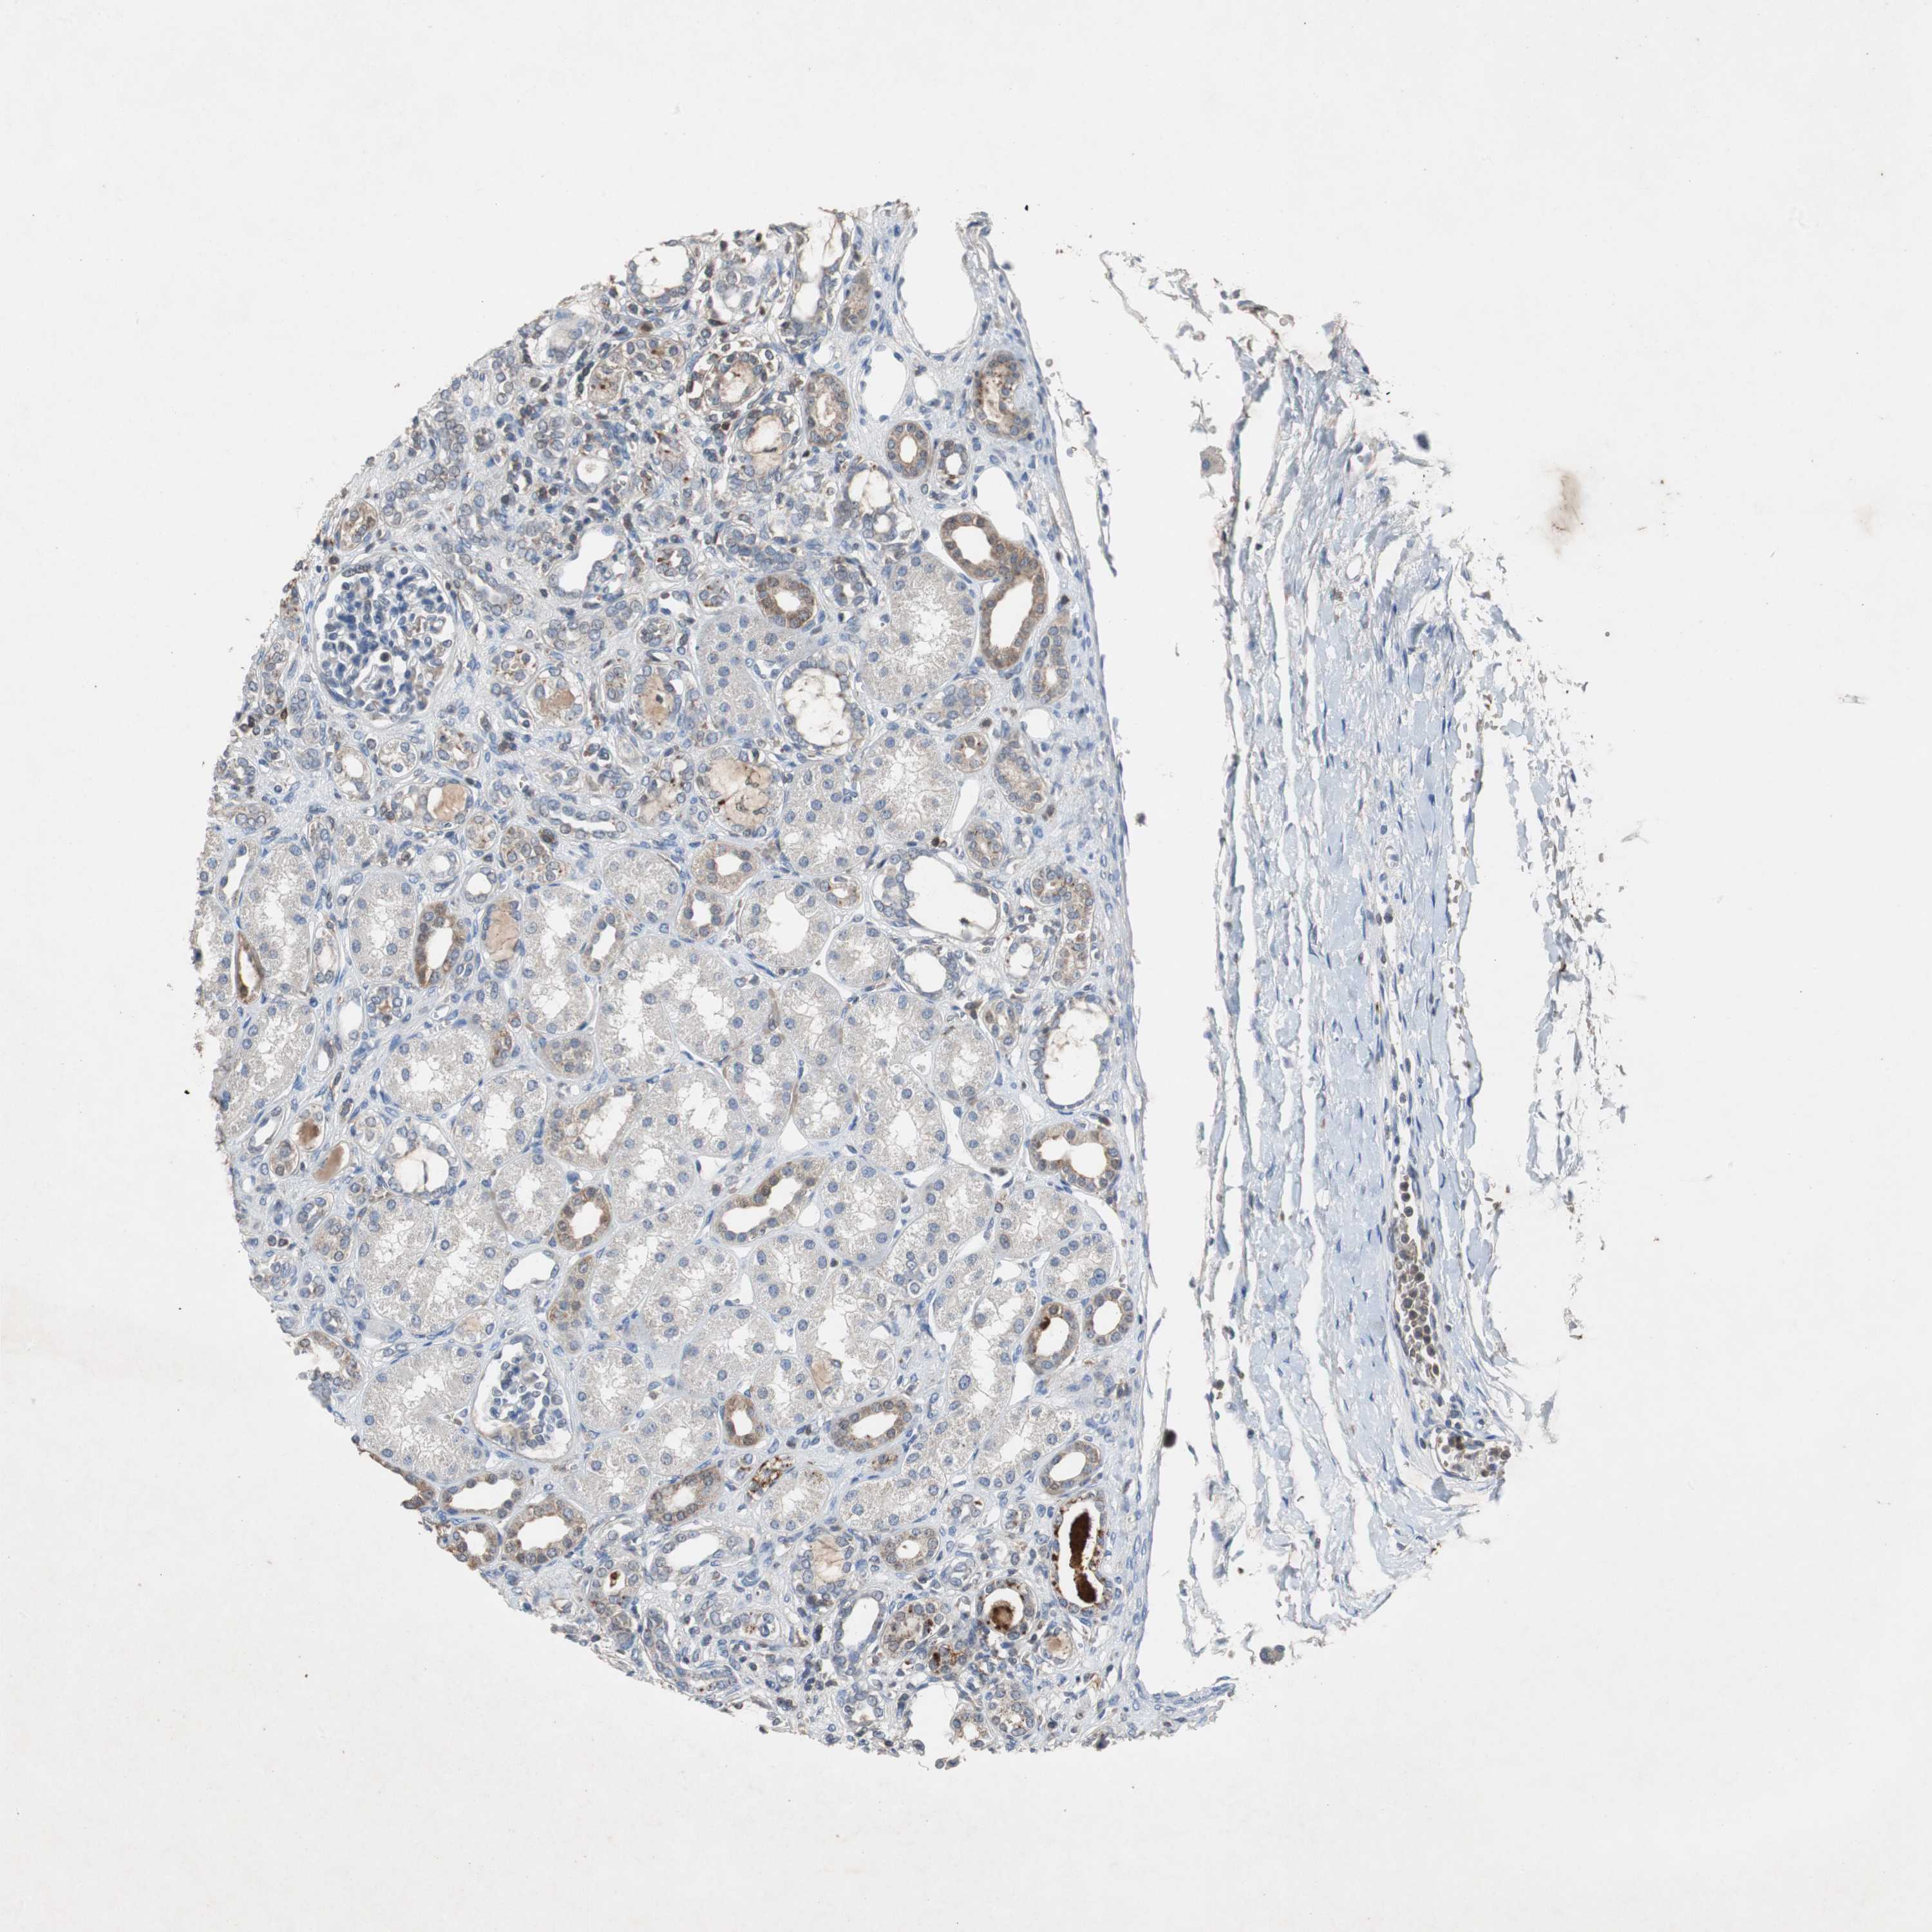

KIDNEY - Antibody stainingi

Antibody staining in the annotated cell types in the current human tissue is reported as not detected, low, medium, or high, based on conventional immunohistochemistry profiling in selected tissues. This score is based on the combination of the staining intensity and fraction of stained cells.

Each image is clickable and will lead to virtual microscopy that enables deeper exploration of all samples and also displays staining intensity scores, fraction scores and subcellular localization as well as patient and tissue information for each sample.

Antibody HPA007305Antibody HPA007306Antibody CAB000106

Cells in glomeruli Not detectedNot detectedNot detected

Cells in tubules MediumMediumNot detected